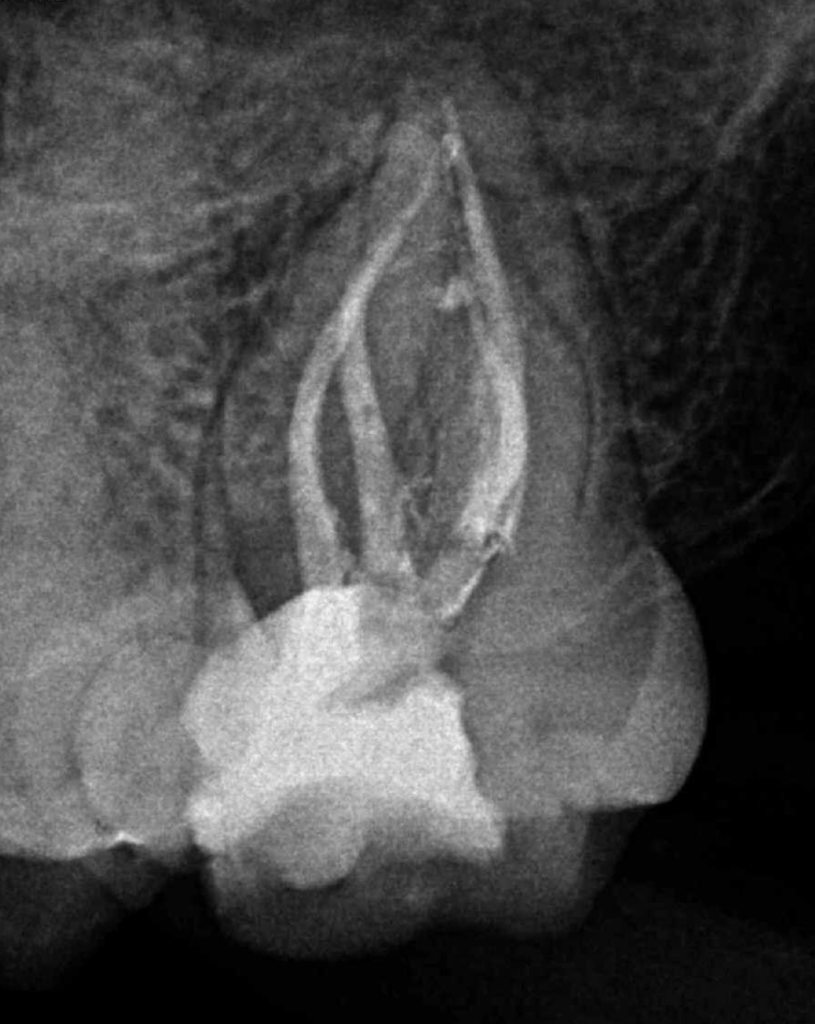

Reco preendo + 4 conductos molar superior